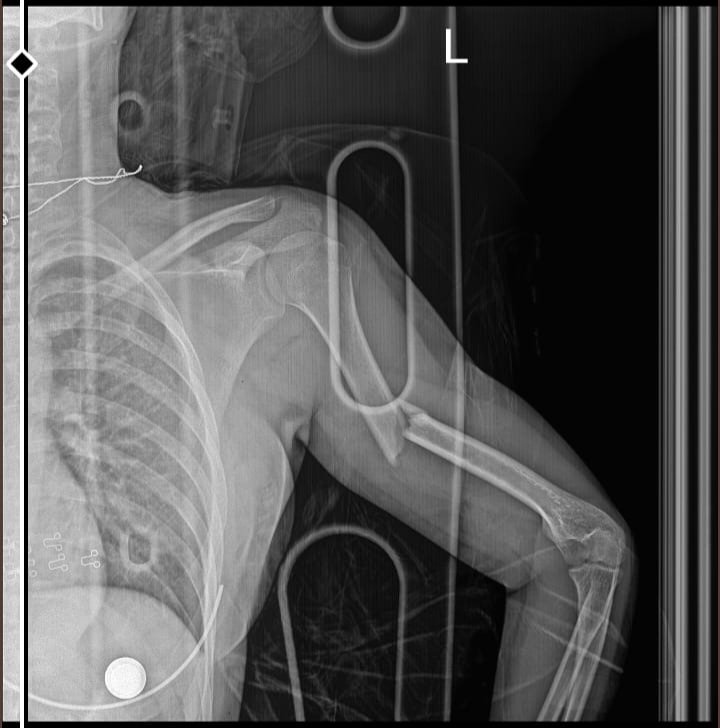

Aslında kendim için sordum, bundan 10 ay önce araba çarpması sonucu kolum 3 ayrı yerden kırıldı ve ameliyat olmam gerekti, 4 vida ve humenus çivisi var, kolum için fizik tedavi bile gerekti ama 10 ayın ardından hala acıyor, bazen kaldırdığımda, bir şey taşırken yada durup dururken. Eski halini alıcak mı yoksa ara ara kendini hissettiricek mi?